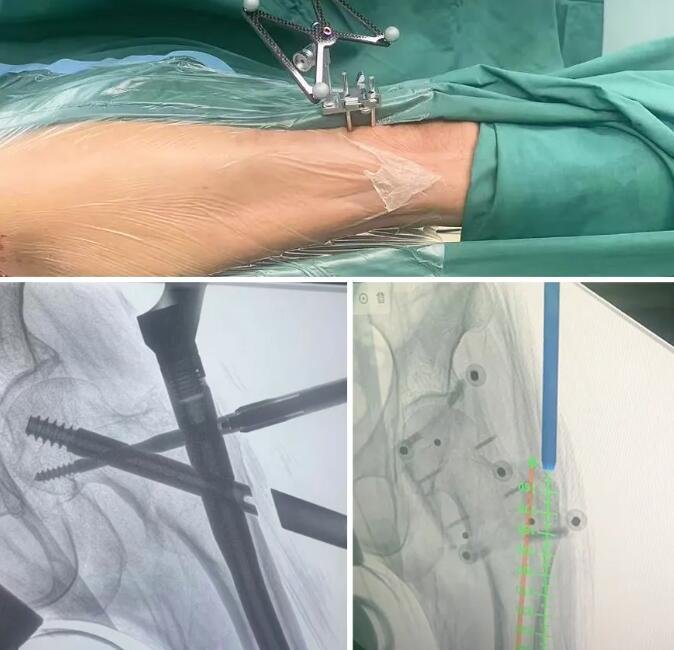

微创+计算机导航,4个「针眼」搞定手术

如何在保障生命安全的前提下实施精准的手术治疗?在任海东主任的带领下,朱宏副主任医师、周立国副主任医师、周蒙恩主治医生组成的手术团队决定采用计算机导航辅助手术。

计算机导航仿佛给医生佩戴了“瞄准镜”,使手术更加精准细致。困难的手术简单化、数字化、智能化,同时缩短了手术时间、减少术中出血量。患者损伤小,术后恢复更快。

术中,骨折闭合复位后,在计算机导航下进行骨折部位数据采集、模拟规划,精准引导髓内钉主钉置入、远端锁定等关键操作。手术实施精准,显著减少了透视辐射量,仅用4个2cm左右的“针眼”轻松完成手术。

通过4个2cm创口完成手术